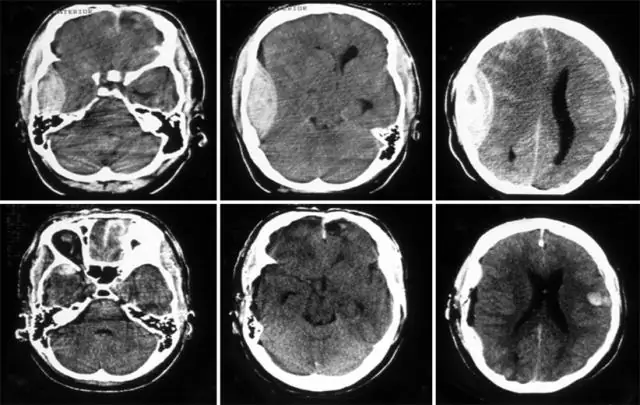

В отличие от черепно-мозговой травмы, ишемический инсульт, как правило, поражает одно полушарие головного мозга, и, таким образом, целью операции является декомпрессия соответствующей области (рис. 2). Поэтому типичной операцией, выполняемой у таких пациентов, является лобно-височно-теменная декомпрессивная гемикраниэктомия. Хотя технические детали, конечно, различаются у отдельных хирургов или центров, этот краткий план описывает типичную операцию: процедура выполняется в положении лежа на спине, голова повернута в противоположную сторону. Широкий изогнутый разрез выполняется либо за ухом, либо перед ним (рис. 3а). Лоскут скальпа и височная мышца затем отклоняются, чтобы обнажить череп. Отверстия для заусенцев создаются и впоследствии соединяются для достижения передне-заднего диаметра области краниэктомии не менее 12 см, при этом рекомендуемый диаметр у взрослых пациентов с ЧМТ составляет 15 см (рис. 3b) (18). Наконец, DC расширяется, чтобы обнажить дно средней черепной ямки (Fig. 3c). Краниэктомия подходящего размера необходима для достижения желаемого декомпрессивного эффекта. Более того, неоптимальный ДК приведет к обострению внешней грыжи головного мозга и сдвиговых сил на краях кости, что может вызвать внутрипаренхиматозное кровоизлияние и излом мозговых вен (19).

Декомпрессивная гемикраниэктомия при злокачественном ишемическом инсульте. Аксиальная компьютерная томография перед операцией (а), демонстрирующая четко выраженный правосторонний инфаркт MCA (выделено красным) с геморрагическим преобразованием (черная стрелка) и смещением средней линии влево (красная линия). Аксиальная компьютерная томография после операции (b), показывающая дефект краниэктомии (выделено зеленым цветом) с декомпрессированным боковым желудочком (выделено синим цветом) и реверсирование сдвига средней линии (зеленая линия)

Изображение в полном размере